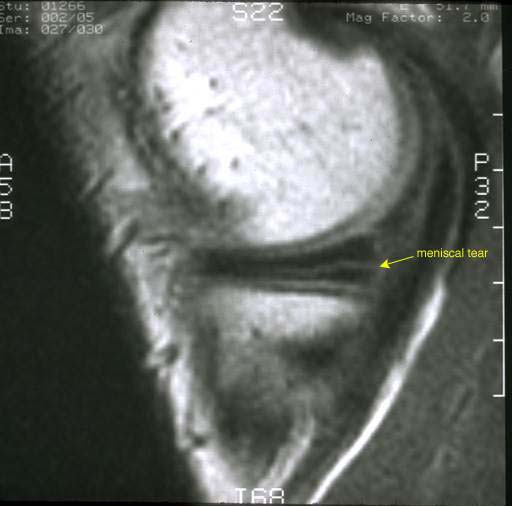

What is a meniscal tear? Ultrasound Guided Injections